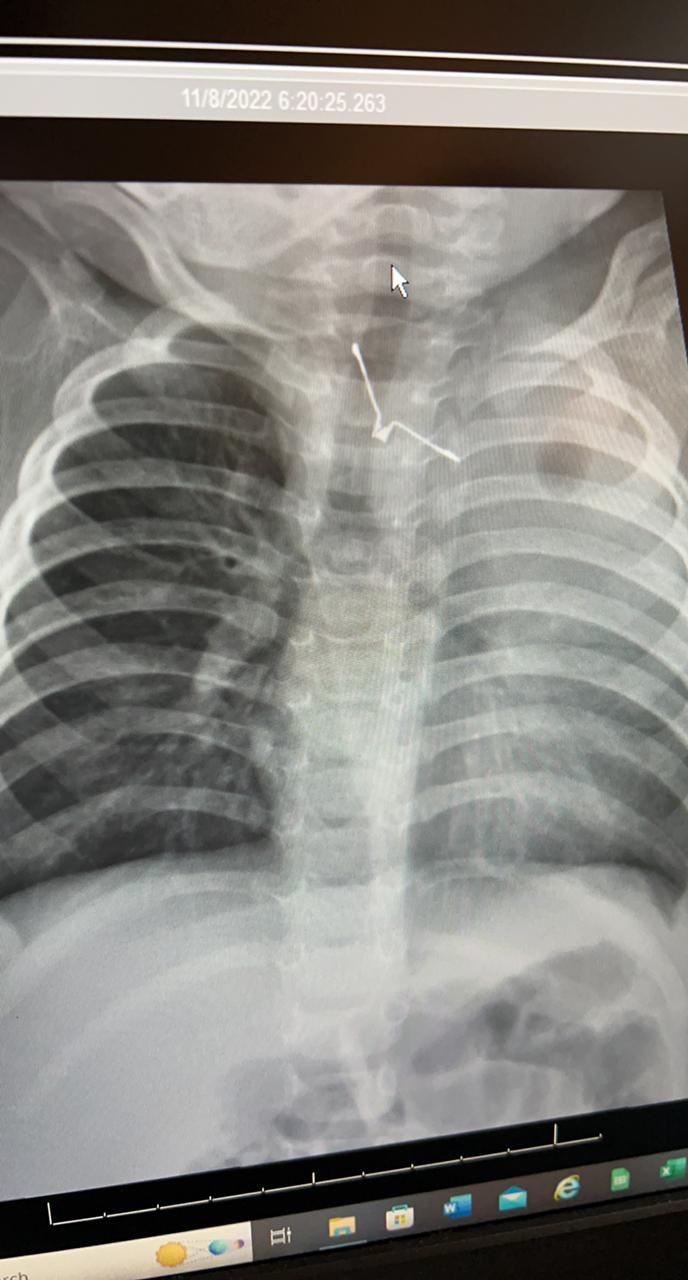

وأوضحت أن الفريق الطبي المشرف على الحالة قام على الفور بعمل التحاليل والإشاعات اللازمة، وتم إدخال الطفلة لغرفة العمليات بشكل عاجل؛ وذلك لاكتشاف جسم معدني حاد الأطراف بلعته الطفلة، وبقي عالقاً في المرئ، مما يسبب لها مضاعفات صحية خطيرة، لو تم تحريكه بأي طريقه خاطئة.

وأفادت الصحة بأن الفريق الطبي نجح في مده زمنية تقارب الـ (4) ساعات من إخراج الجسم الغريب بالمنظار وبحذر شديد؛ حتى لاتصاب الأنسجة المحيطة به بأي جروح، وتتمتع الطفلة حاليًا بصحة جيدة ومازالت تحت العناية لإكمال فترة الشفاء.